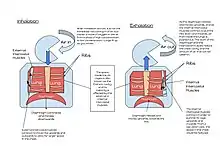

The lungs are not capable of inflating themselves, and will expand only when there is an increase in the volume of the thoracic cavity.[6][7] In humans, as in the other mammals, this is achieved primarily through the contraction of the diaphragm, but also by the contraction of the intercostal muscles which pull the rib cage upwards and outwards as shown in the diagrams on the right.[8] During forceful inhalation (Figure on the right) the accessory muscles of inhalation, which connect the ribs and sternum to the cervical vertebrae and base of the skull, in many cases through an intermediary attachment to the clavicles, exaggerate the pump handle and bucket handle movements (see illustrations on the left), bringing about a greater change in the volume of the chest cavity.[8] During exhalation (breathing out), at rest, all the muscles of inhalation relax, returning the chest and abdomen to a position called the "resting position", which is determined by their anatomical elasticity.[8] At this point the lungs contain the functional residual capacity of air, which, in the adult human, has a volume of about 2.5–3.0 liters.[8]